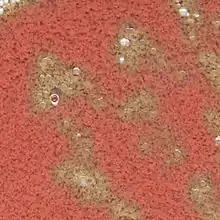

Agar chocolate con colonias visibles de Francisella

Estas bacterias necesitan factores de crecimiento, como el NAD y hemina, componentes que podemos encontrar dentro de los glóbulos rojos; por lo tanto, un prerrequisito lógico para el crecimiento es la lisis de los glóbulos rojos. El agar se llama así debido a su parecido con el chocolate, pero no contiene nada de este.